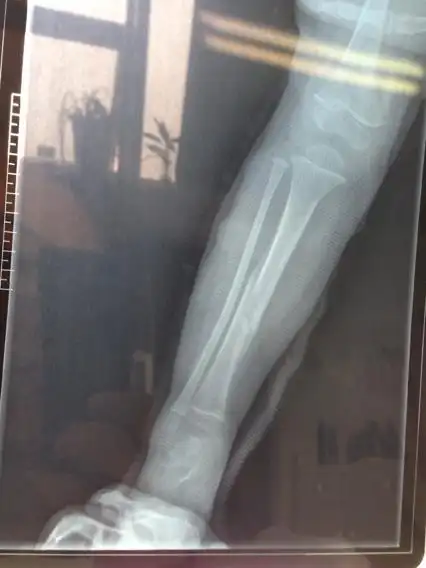

小腿骨骨折医学上称为胫腓骨骨折,大部分可采用微创 - 抖音

原创小腿远端粉碎骨折

创伤左小腿开放性骨折

本人男,19岁,小腿胫骨骨折100天,请大家看看怎么样?

这是我右腿粉碎性骨折的照片,大家看一下,什么时.